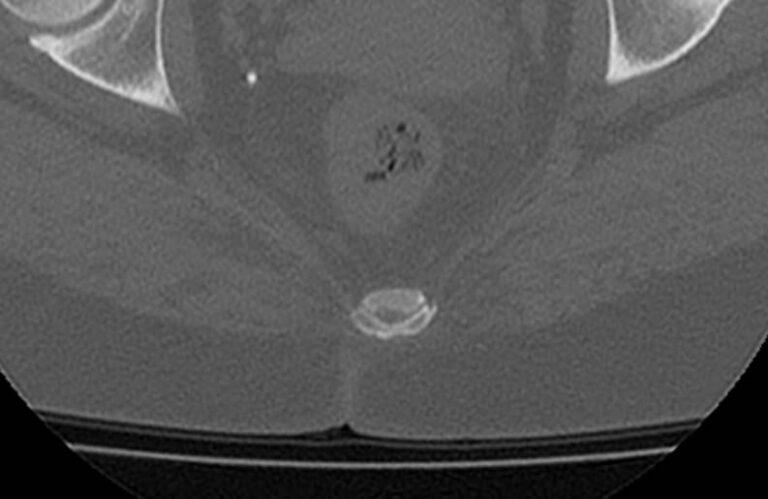

Одним из наиболее информативных методов диагностики заболеваний копчика является мультиспиральная компьютерная томография. Метод основан на использовании рентгеновского излучения и применения инновационных компьютерных программ для детальной визуализации состояния органов и систем организма. Процедура отличается быстротой, безболезненностью и неинвазивностью (то есть проводится без нарушения целостности кожи и расположенных под ней тканей).

Инновационные возможности аппаратов дают возможность получить множество послойных снимков высокого качества и реконструировать на их основе трехмерную модель органа. Кроме того, аппаратура позволяет за счет сокращения времени сканирования максимально уменьшить лучевую нагрузку на пациента.

Что покажет КТ копчика

- перелом крестца или копчика, смещение позвонков и другие травмы, в том числе застарелые.